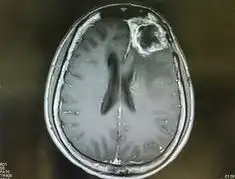

4. 진단은 MRI, CT 스캔을 통해 이루어지며, 조직 검사로 확진합니다.

교모세포종의 진단은 주로 고해상도의 영상 진단 도구인 MRI 또는 CT를 통해 이루어집니다.

이러한 검사를 통해 종양의 위치, 크기 및 주변 조직과의 관계를 정확히 평가할 수 있습니다.

또한, 최종적인 진단을 위해서는 조직 검사가 필수적으로 수행됩니다.